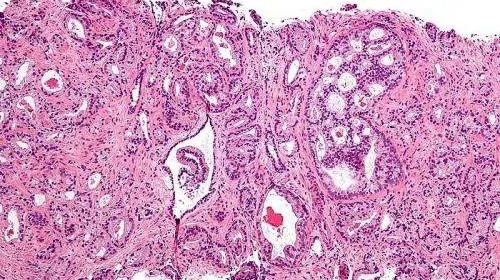

【新进展】英国科学家发现了前列腺癌的新药物靶标!

早在2019年,波士顿大学医学院(BUSM)的研究人员就提出,阻断特定蛋白可能是防止去势抵抗前列腺癌(CRPC)传播的一种有前途的策略。抑制蛋白BRD4而不是BRD2或BRD3,可以稳定地调节前列腺癌细胞的迁移和侵袭。

CRPC是一种复杂的异质性疾病,在单个肿瘤细胞中具有不同的AR状态和表达模式。随着疾病的发展,前列腺肿瘤细胞对AR信号的依赖性会降低,并使用其他信号机制来维持生长和扩散。因此,在依赖或独立于雄激素受体信号转导的细胞中,确定调节前列腺癌细胞迁移和侵袭的药物靶点是至关重要的。这一发现在2019年5月20日在线发表在《分子癌症研究》杂志上。

*近,波士顿大学医学院的研究人员研究发现,BRD4蛋白可能是防止去势抵抗前列腺癌转移的一个重要新靶点。

去势抵抗前列腺癌是一种高度侵袭性的前列腺癌,通常会出现致命性转移,美国每年有超过31,000名男性死于去势抵抗前列腺癌。去势抵抗前列腺癌患者的治疗标准通常包括使用“雄激素剥夺疗法”扰乱雄激素受体信号。虽然这种疗法的平均疗效为2 - 3年,但由于对药物的获得性耐药,这种疗法*终无法阻止癌症的进展。然后病人就会转移,继而无法治愈。

在BUSM的医学和药理学副教授Gerald V. Denis博士的指导下,研究人员长期研究了一个由BRD2、BRD3和BRD4组成的名为BET溴域蛋白的三种密切相关的蛋白质家族,它们调节基因表达。BUSM的研究人员在20世纪90年代首次展示了这些蛋白质在人类癌症中的作用。

研究人员对前列腺癌细胞系进行了研究,这些细胞系模拟了对雄激素剥夺疗法有抵抗力的常见前列腺癌,发现BRD4,而不是类似的家族成员BRD2或BRD3,调节直接导致前列腺癌进展的关键蛋白的表达。

BUSM分子和转化医学系的研究员、该研究的**作者乔丹·沙夫兰(Jordan Shafran)解释说,“这些发现是新颖的,因为到目前为止,还不清楚BET蛋白家族中的哪一个调控转录程序,或者它们如何影响前列腺癌细胞的形态(形状和极性)、能动性(独立移动的能力)和侵袭性,每一个都与转移能力有关。”

研究人员表示,这些发现具有重大意义,因为目前针对去势抵抗前列腺癌的治疗选择有限,主要集中在抑制依靠雄激素受体信号传导的前列腺肿瘤细胞。随着前列腺肿瘤细胞对治疗产生耐药性,它们对雄激素受体信号的依赖减少,替代信号机制被激活。在这种复杂的混合物中,转移细胞就出现了。

研究人员认为,为了阻止前列腺癌细胞的迁移、侵袭和*终的转移,必须找到新的靶点来调节关键转录因子在不同类型前列腺癌细胞中的表达。